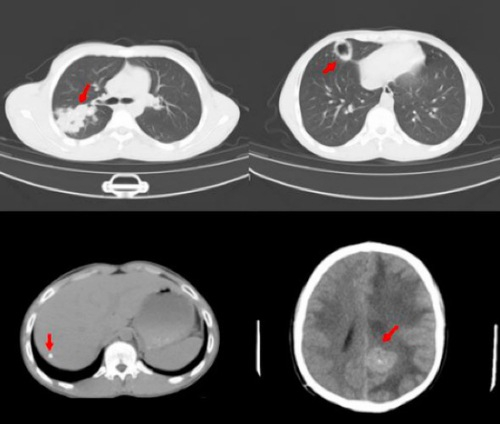

咳嗽、咳痰伴背部疼痛、盗汗,吉桑难受了一个来月。3月,他来到青海省果洛州人民医院就诊,肺部CT发现明显病灶,当地医务人员初步考虑结核。然而抗结核治疗后病情不见好转,进一步检查时,颅内、肝脏又发现了病灶,其中颅内病灶已表现出占位效应,小伙子随时可能有性命之虞。多脏器累及的病灶元凶究竟是什么,当地医生犯了难。

吉桑的CT影像资料

幸运的是,身在果洛的吉桑,得到来自2749公里之外上海大医院专家的医疗帮助。4月11日下午,在复旦大学附属华山医院远程会诊中心,神经外科专家周良辅院士、放射科专家耿道颖教授、感染科专家张文宏教授联合会诊。三位专家结合患者的流行学资料、影像学表现和既往病史,与当地医生充分讨论,缜密分析,很快得出一致意见:考虑为播散性包虫病,并给出进一步检查和药物、手术治疗建议。